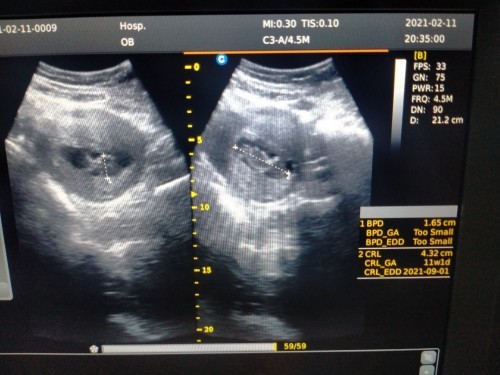

Bunda2,, mau nanya nih.. apakah ada yg sma sprti sya, stelah USG kmren dokter bilang klo usia kehamilan sya 3 bulan/12minggu,. Sdangkan klo d hitung dr Hari trakhir mens itu kta bidan udh 14 minggu.. Dan ini kmren hasil USG.nya,, NormalKah Bund d liht dr CRL.nya?? Krna sya hbz browsing ktax klo usia 12 minggu CRl.nya itu 5,4cm.. Bantu jwb yaa bund🙏#seriusnanya